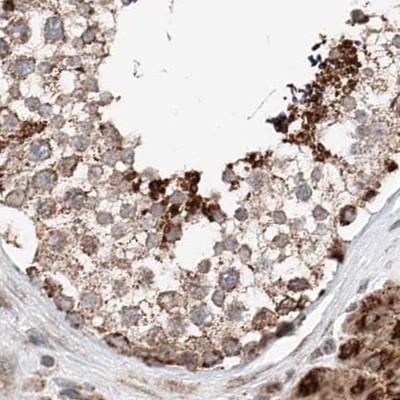

Immunohistochemical staining of human colon, kidney, liver and testis using Anti-ZSCAN29 antibody HPA011109 (A) shows similar protein distribution across tissues to independent antibody HPA007241 (B).